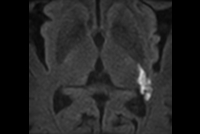

IAC lesion with Compressed SENSE